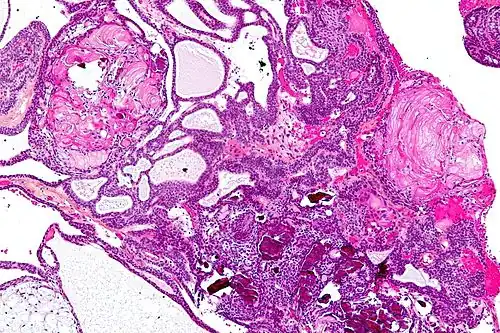

Very low magnification micrograph of an adamantinomatous craniopharyngioma. HPS stain.

In some cases, a powerful 3T (Tesla) MRI scanner can help define the location of critical brain structures affected by the tumor. The histologic pattern consists of nesting of squamous epithelium bordered by radially arranged cells. It is frequently accompanied by calcium deposition and may have a microscopic papillary architecture. A computed tomography (CT) scan is also a good diagnostic tool, as it detects calcification in the tumor.[21]

• Adamantinomatous craniopharyngiomas, which resemble ameloblastomas (the most common type of odontogenic tumor), are characterized by activating CTNNB1 mutations.

On macroscopic examination, craniopharyngiomas are cystic or partially cystic with solid areas. On light microscopy, the cysts are seen to be lined by stratified squamous epithelium. Keratin pearls may also be seen. The cysts are usually filled with a yellow, viscous fluid rich in cholesterol crystals. Of a long list of possible symptoms, the most common presentations include headaches, growth failure, and bitemporal hemianopsia.